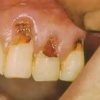

Hambaauk

Hambaauguks ehk kaariesekahjustuseks nimetame hamba kõvakoe kahjustust, mille on põhjustanud hambapinnal elava mikroobiikihi ehk biofilmi elutegevuse jääkaine - piimhape. See hape söövitab hambakude ehk lahustab sellest välja mineraale, mille tagajärjel...